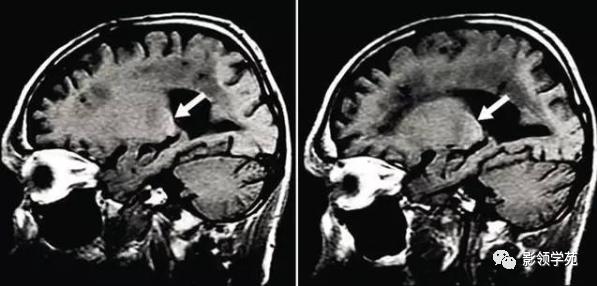

图 8 肝性脑病(锰沉积)患者显示双侧苍白球对称性 T1 高信号

此外,没有总结进去的还有非酮症糖尿病偏侧舞蹈导致的单侧或双侧基底节区 T1WI 高信号,以及Fabry 病(α-半乳糖苷酶 A 缺乏病)导致的较有代表性的丘脑枕 T1WI 高信号。